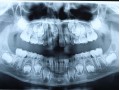

Rozległa torbiel zawiązkowa żuchwy

Paulina Adamska, Maria Mikołajska, Anna Janowska, Anna Starzyńska